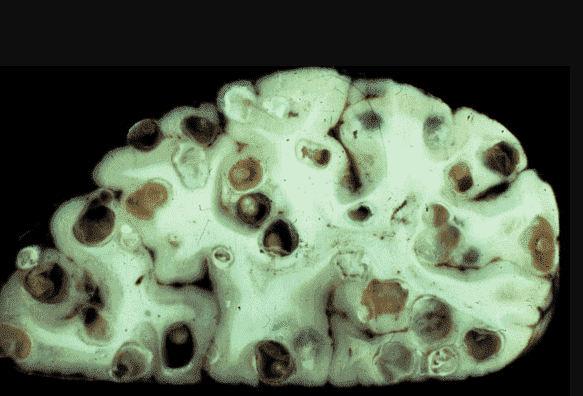

Egy másik eset: egy 61 éves férfi, aki májcirrózisban halt meg. A rokonok szerint az alkohol volt a hibás. Igen, csak nem ivott eleget ahhoz, hogy ez okozza a halálát. A máj alkoholos pusztításának nyoma sem volt, de a máj egyszerűen tele volt parazitákkal, több száz járatot találtam, amelyeken keresztül a férgek mozogtak benne.

A paraziták "útjai" a bél lumenében

Leggyakrabban a belekben kezdődik. A paraziták a szájon keresztül jutnak be a tápcsatornába, és problémát okoznak. Később más szervekbe is bejuthatnak, kiterjedt elváltozásokat okozva. Nézze meg az alábbi képeket.